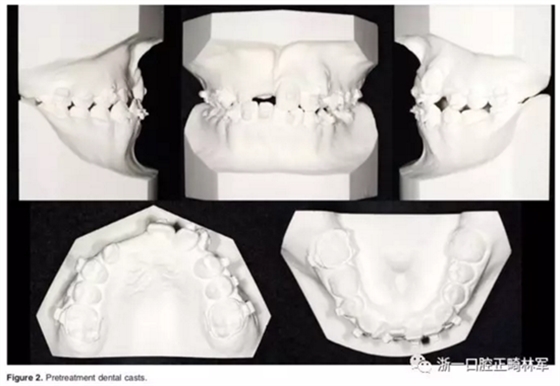

口內相示:替牙晚期,11-13未萌,磨牙端端關系,前牙擁擠嚴重,23高位,53、75滯留;患者正采用固定矯治,部分托槽有脫落。

全景X片及CBCT示:11-13復雜阻生,上頜前牙區(qū)牙槽骨水平不足;11阻生,遠中旋轉90°,牙冠朝向腭側,根尖位于鼻底、前鼻棘皮質骨內,牙根形態(tài)彎曲;12、13不完全易位,12位置偏腭側,13位置偏舌側,12的牙根形態(tài)也較彎曲。

診斷:骨性I類,牙性II類,高角,多牙阻生,面部不對稱(右偏),上下切牙直立。